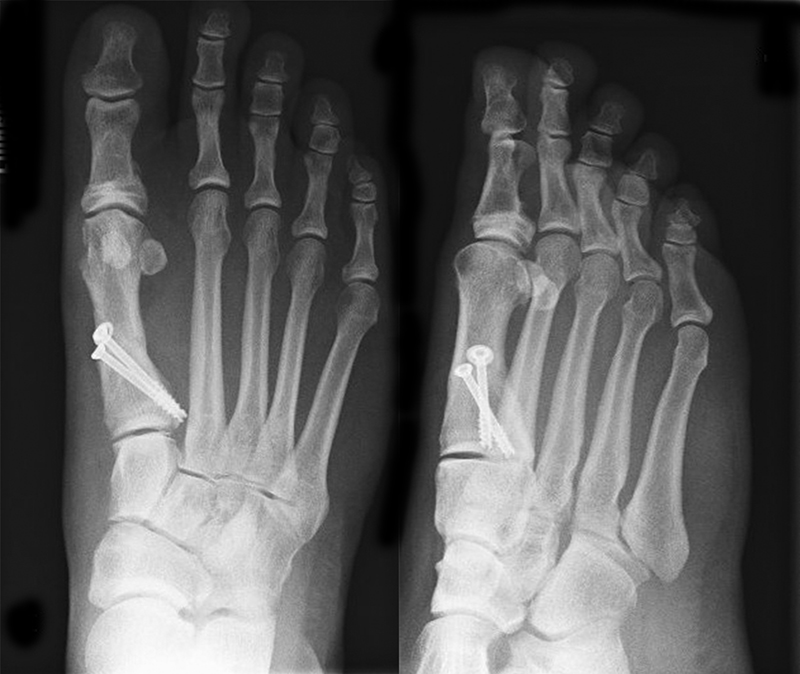

• Kanülierte Schrauben bis 50 mm Länge, 4 mm Durchmesser, Beilagscheiben.

• Röntgenkontrollen (Vorfuß d.p. und seitlich) postoperativ ohne Belastung. Weitere Kontrollen erfolgen 6 Wochen, sowie 3, 6 und 12 Monate jeweils unter Belastung.